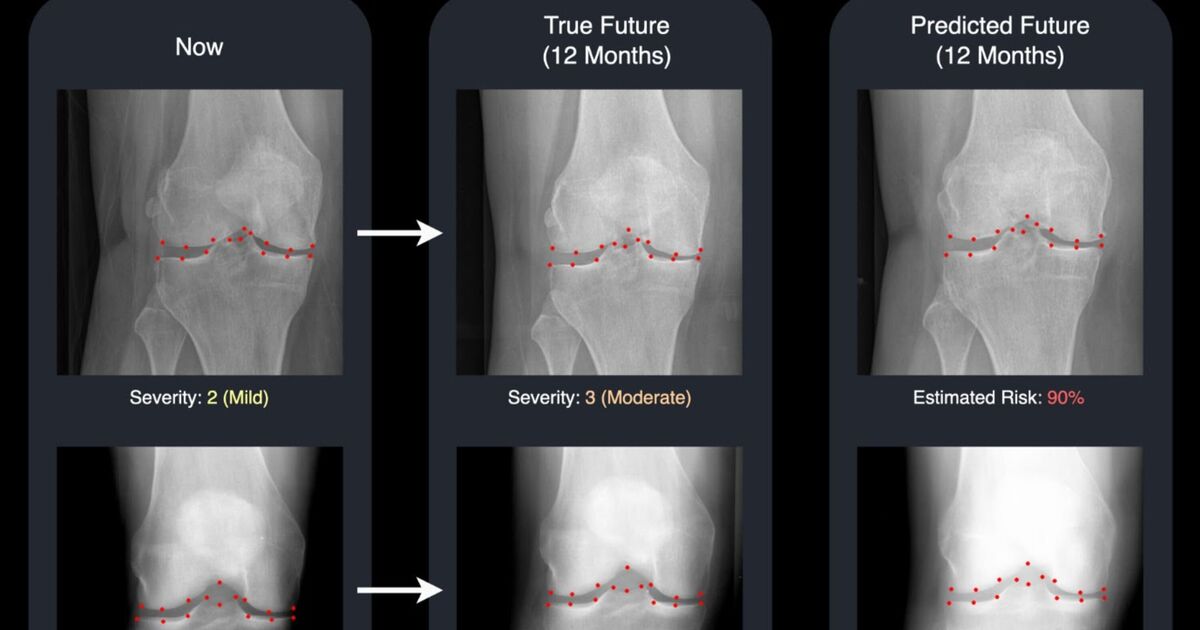

A groundbreaking study from the University of Surrey has introduced a technology that utilizes advanced machine learning techniques to create a realistic “future” X-ray, coupled with a risk score indicating the disease’s progression in the knee. This dual output provides doctors and patients with a clear and visual outlook on how the condition might evolve over time.

Using an advanced generative model, called a diffusion model, the Surrey system generates a “future” version of a patient’s knee X-ray and highlights 16 key points in the joint.

These points add transparency by showing which areas the AI is monitoring for changes, making the system easier for clinicians to understand and trust.

David Butler, leading post-graduate researcher at the University of Surrey’s Centre for Vision, Speech and Signal Processing (CVSSP) and Institute for People-Centred AI, noted: “Typically, medical AI tools provide a numeric prediction with little context.

“Our system goes a step further by not only assessing the likelihood of knee deterioration but also generating a realistic image of what the future condition might appear like.”

“Seeing the two X-rays side by side – one from today and one for next year – is a powerful motivator.